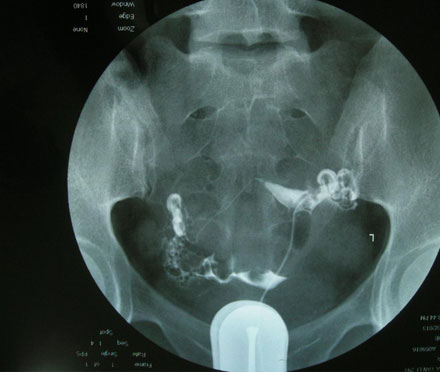

输卵管是精虫与卵子相遇的通道,因此输卵管畅通与否会决定后续的治疗方向。若是畅通,可选择简易辅助受孕或人工受孕;若有阻塞或水肿现象,不仅会增加宫外孕的风险,这些内含发炎物质的液体若流入子宫腔,将影响胚胎的着床与发育。建议最佳的处理方式是将阻塞积水的输卵管做截断或切除,并利用试管婴儿技术,提高成功受孕的机会。